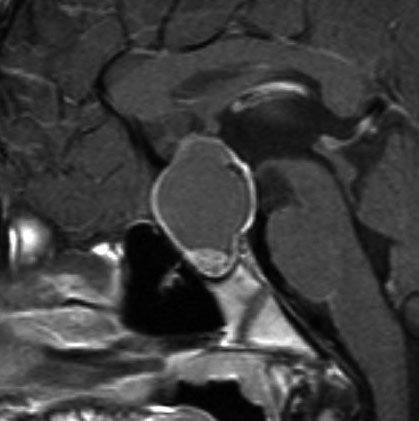

8歳で両側の視力低下が生じました。眼科では精神的なものと診断されて,4ヶ月くらいで右視力 0.4(耳側半盲),左指数弁となりました。のう胞性頭蓋咽頭腫で大きな骨化を伴うもので1月くらいの間に全盲になるかもと判断しました(失明寸前です)。

矢印の先に見えるように下垂体は正常の形態です。この画像から灰白隆起の左後方,乳頭体の前方が腫瘍発生母地ということがわかります。尿崩症もなく下垂体機能は正常です。経鼻的な内視鏡手術で腫瘍の大部分を摘出すれば下垂体機能は廃絶します。

とにかく失明を避けるために急いで経蝶形骨洞手術(transsphenoidal-transtuberculum sellae approach)で腫瘍のう胞の減圧をしました(緑の矢印の経路 by 函館中央病院加藤功先生)。その後に前頭開頭で腫瘍を全摘出しました(右側の画像)。尿崩症はでましたが下垂体前葉機能は正常です。

右視力 0.45,左明暗弁の視力が残りました。でももし,経鼻手術をしないでいきなり開頭すればおそらく全盲になっていた例です。